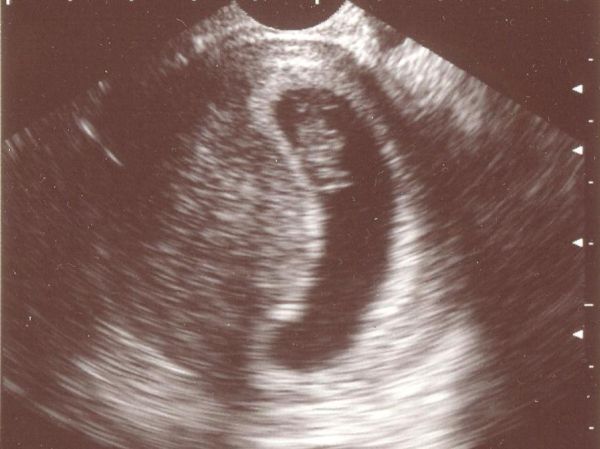

Küldöm majd az adatokat! Látszódik ám a baba az UH képen, nagyon édes!

Csak ketten voltak az elejétől fogva ( vagyis elsőnek 3, de két babóca választott minket), az UH képen valami ufós dolog látszik még, őszintén nem tudom, hogy mim az!